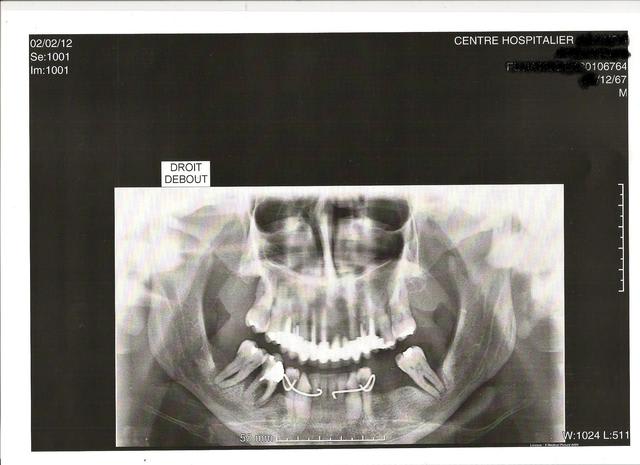

Bref , j'ai demandé une pano de qualité !

Pano b mtqyzv - Eugenol

Bref, t'as eu une pano de qualité!